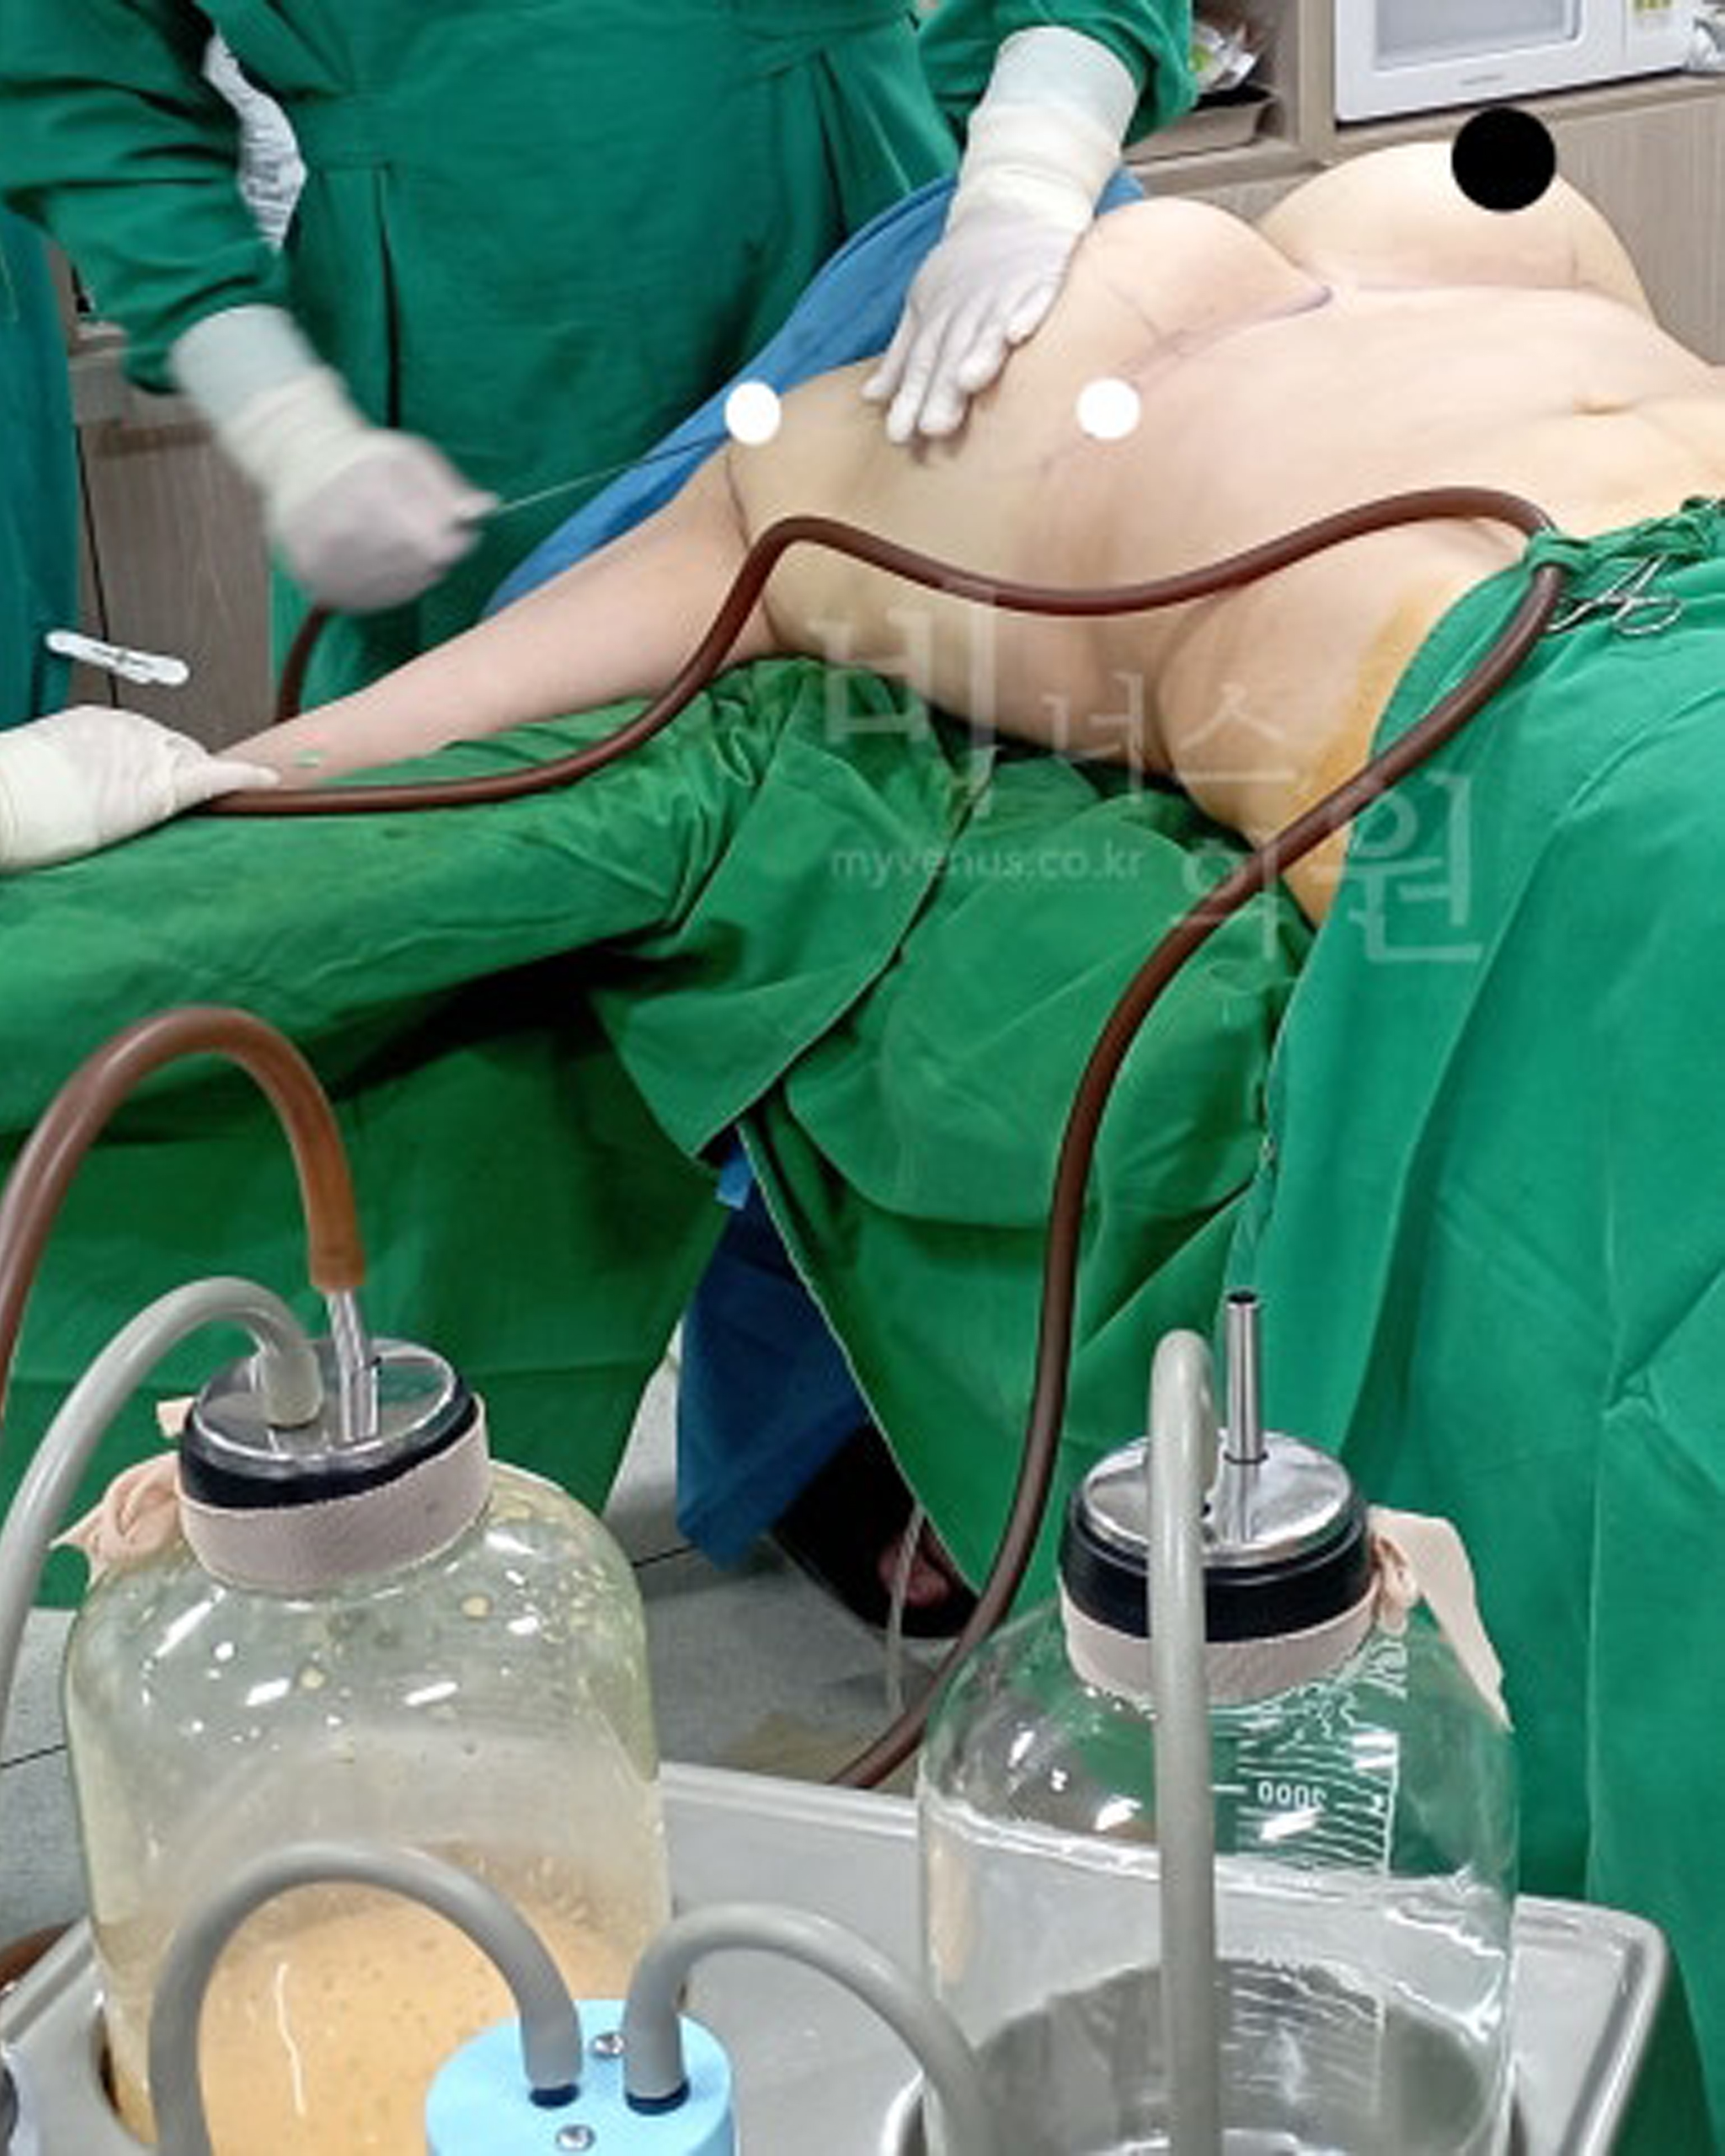

사이즈 감소가 확실한 가슴축소

가슴의 지방이 흡입되고 있는 모습

지방만을 흡입한 가슴축소 지방흡입

가슴축소 지방흡입이 끝난 직후의 모습

지방흡입을 통한 가슴축소 지방량

노란 지방량이 흡입된 모습

절개법의 경우 지방층 뿐만 아닌 유선 조직을 잘라내야 하는 경우도 있으므로 수유장애 등의 위험도도 있을 수 있지만, 가슴 지방흡입의 경우 지방만을 흡입하기 때문에 향후 분만 계획이 있거나 미혼 여성에게는 권해드릴 수 있는 큰 장점이 있어요.